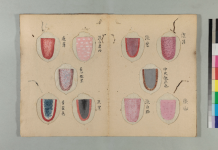

格致餘論:治病先觀形色然後察脈問証論 其之一

經曰:診脈之道,觀人勇怯,

肌肉皮膚,能知其情,以為診法也。

凡人之形,長不及短,大不及小,肥不及瘦。

人之色,白不及黑,嫩不及蒼,薄不及厚。

而況肥人濕多,瘦人火多,白者肺氣虛,黑者腎氣足。

形色既殊,髒腑亦異。外証雖同,治法迥別。

所以肥人貴脈浮,瘦人貴脈沉,躁人疑脈緩,

緩人疑脈躁,以其不可一概觀也。試陳一二,可以例推。

素問に基づいた望診と脈診で

人を診ていくことの大事さを説いております。

※画像や文献に関して、ご興味がおありの方は

是非参考文献を読んでみて下さい。